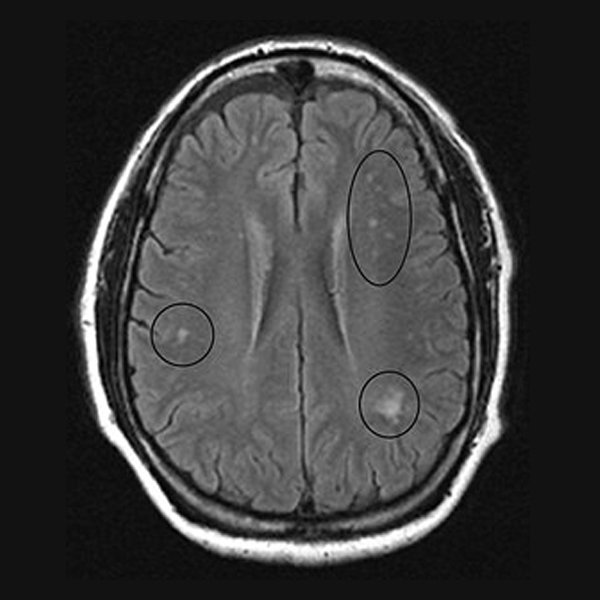

Vitamin B12 Deficiency Can Lead to Reversible Basal Ganglia Changes in Vitamin B12 Deficiency Case Study with this case study, we want to highlight the importance of recognising the clinical significance of vitamin b12 deficiency and. in this review, we focused our attention on some case reports related to the vitamin b 12 deficiency associated to. During the 1940s, an intensive search for the active factor in liver extracts that prevents pernicious anemia. . Vitamin B12 Deficiency Case Study.